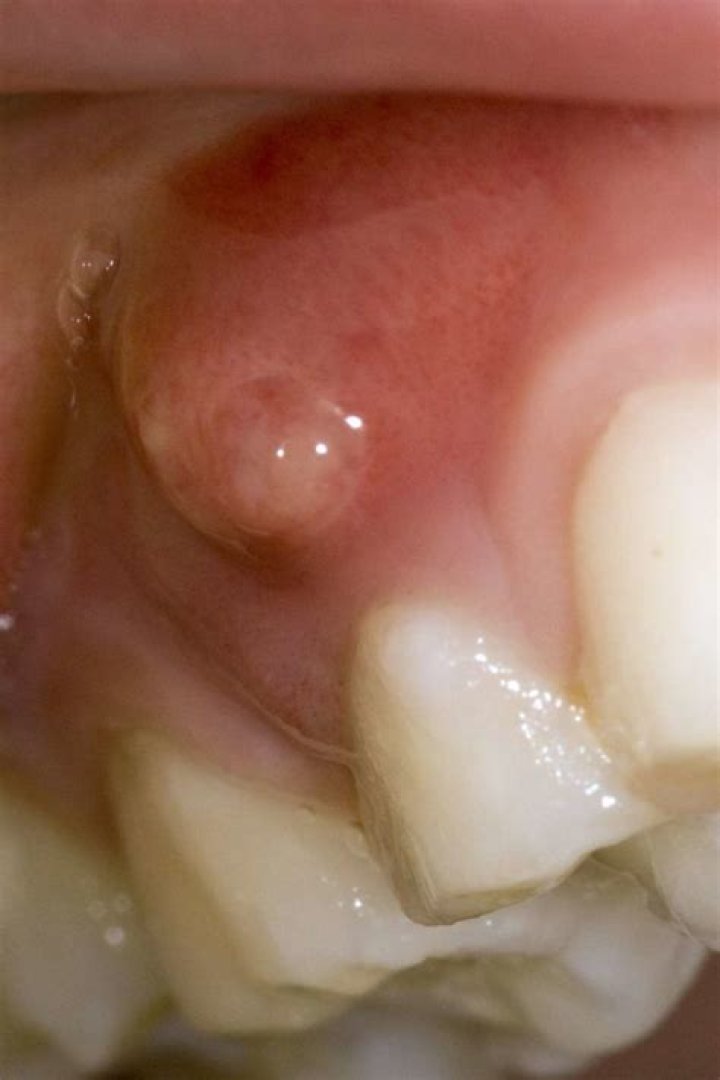

What does a cyst in your mouth look like?

They are lumps or sacs filled with mucus. Mucous cysts might look bluish in color. If there's bleeding into the cyst, it might appear red. Other times they are translucent or white.

What does a gum boil look like?

A gum boil, or parulis, is a localised concentration of pus which occurs in the soft tissue of the gum. Gum boils usually look like a small pimple in the mouth, and are drainage points for abscesses which occur in the roots of the teeth.

What does a gum abscess look like?

What does a gum abscess look like? It may start as a shiny, reddened area of your gum tissue. As the abscess progresses, a tiny white or yellow dot may appear on your gums, gradually getting larger as the abscess fills with pus. Eventually, the abscess will resemble a pimple on the gum.